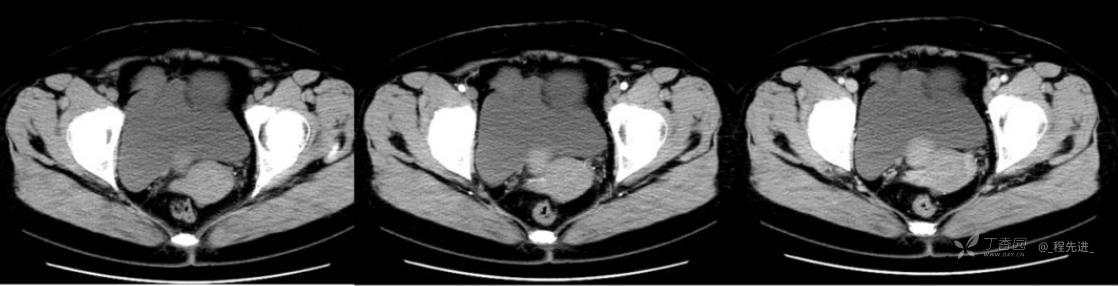

1月特别精彩病例|中老年女性,盆腔包块近半年持续增大【病理已公布】

患者年龄:53岁

简要病史:4年前体检时发现盆腔包块及子宫肌瘤,近半年复查盆腔彩超发现包块持续增大,近1年月经欠规律,伴腰、腹胀。

体格检查:宫颈举痛(+),子宫增大,质地中等,活动可,无压痛;右下腹轻压痛,无反跳痛,左侧附件区未扪及明显包块,无压痛。

阴式彩超:子宫约65*58*44mm大小,子宫肌层可见多个低回声块影,较大的为35*27mm(位于子宫前壁下段偏右侧壁),边界清,内回声欠均匀,后方回声衰减。考虑子宫多发肌瘤。子宫后壁可见一混合回声包块,大小约31*20mm,边界不清,内呈强弱回声,分布不均,考虑子宫腺肌瘤,其他疾患待删。子宫内膜厚6mm,宫颈可见多个囊性暗区,边界清,内透声好,后壁效应增强,较大的为15*11mm。子宫前方偏左侧可探及一大小89*75mm囊性肿块,边界清,壁薄光滑,内透声好,可见分隔光带